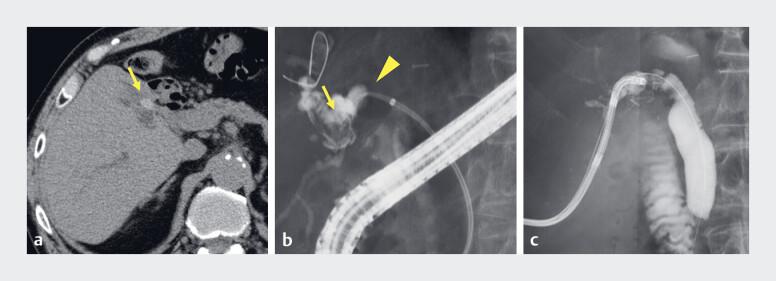

Successful balloon fixation technique to prevent dislocation of a fully covered self-expanding metal stent for biliary stricture.

Endoscopy. 2025 Dec;57(S 01):E88-E89. doi: 10.1055/a-2515-3156. Epub 2025 Jan 31.

Successful balloon fixation technique to prevent dislocation of a fully covered self-expanding metal stent for biliary stricture.成功的球囊固定技术可防止完全覆盖的自膨式金属支架在胆管狭窄中发生移位。